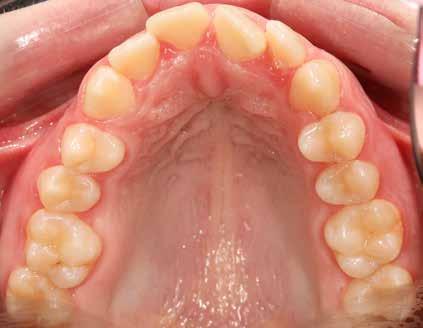

A Pitts21-es fix készülékes kezelés során a harapásemelőket a felső nagyőrlő fogakra ragasztottuk, hogy a felső molárisok intrúziójával segítsék a harapás zárását (8. kép) Ún. keresztharapásos, majd később normál class 2-es gumihúzással (9–10. képek), továbbá az elülső fogakon alkalmazott ún. Rainbow harapás-záró gumihúzással (11. kép) korrigáltuk a jobb oldali teljes premolárisnyi distal-harapást, valamint az elülső nyitott harapást.

6 hónap után a nyitott harapás már nagyjából összezárásra került (12. kép)! A gumihordás a kezelés teljes hosszában folyamatos, éjjel-nappal, 22-24 órában az étkezések és az utánuk történő fogmosás kivételével.